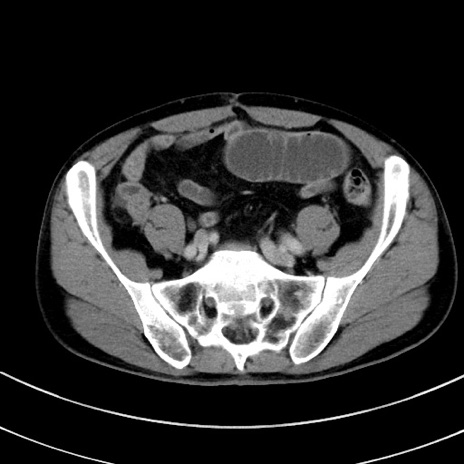

症例8(横断像)

【症例】 60歳代男性

【主訴】 黒色吐物

【現病歴】 4日前から嘔気自覚、2日前の朝食後にも嘔気あり、自分で手で嘔吐反射起こし嘔吐したところ血が混ざっていたため受診。

【既往歴】 5年前汎発性腹膜炎を伴う急性虫垂炎で手術、高血圧、前立腺肥大症、高脂血症

【身体所見】 腹部正中に手術癩痕あり 腹部平坦・軟圧痛なし膨満感あり

【データ】WBC 8400、CRP 4.54